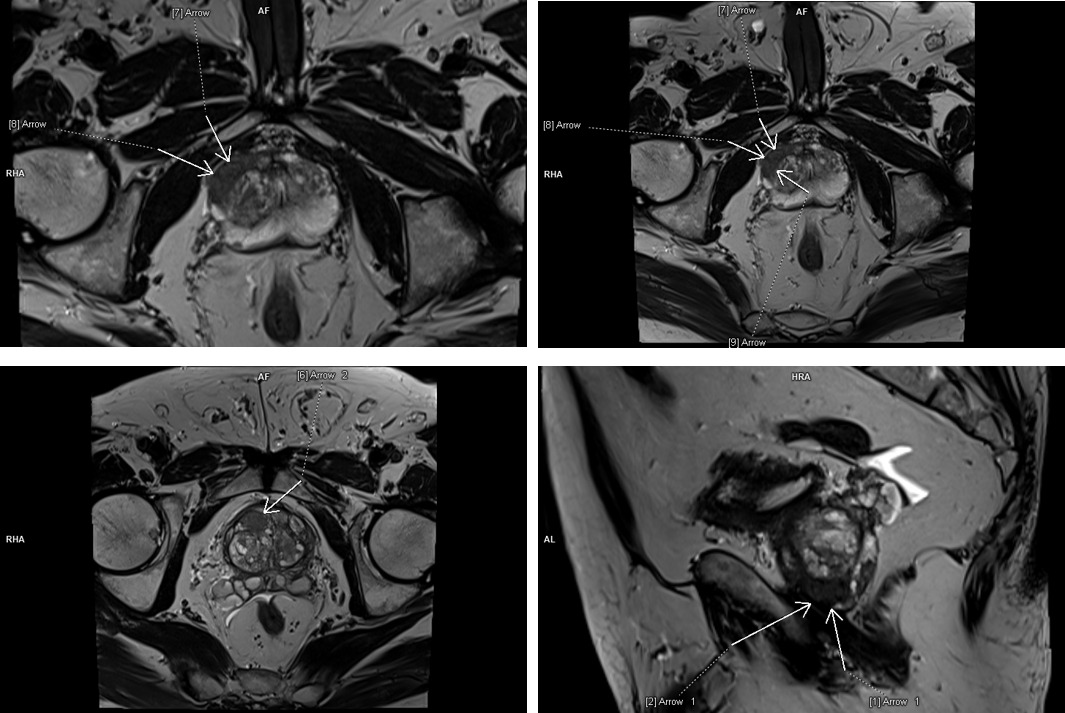

Figura 1: T2 axial si sagital

Figura 2: axial difuzie

Figura 3: axial T1 postcontrast

Discuţie caz nr 80: Pacientul cu suspiciune biochimică de neoplasm prostatic PSA 9.3 ng/ml efectuează examinare IRM multiparametrică și se pune în evidență anterior, la nivelul zonei prostatice superficiale drepte, cu dezvoltare în treimea inferioară şi treimea medie, o leziune de 1.9 cm în hiposemnal T1 cu restricție de difuzie a apei și priză de contrast în timp precoce; dacă acest pacient nu efectua această examinare și medicul urolog făcea puncție biopsie prostatică „în orb” foarte probabil nu se ajungea la diagnostic datorită poziționării anterioare a leziunii.

IRM multiparametric al prostatei este evaluarea inițială a bărbaților fără biopsie cu suspiciune clinică de cancer de prostată. Clasificarea PI-RADS este un sistem pentru raportarea IRM de prostată care își propune să standardizeze tehnica și interpretarea între centre. Leziunile PI-RADS 4 si 5 ridică o suspiciune clinică mare de cancer de prostată şi permite țintirea exactă a locului de punctie-biopsie pentru diagnostic.

DE LUAT ACASĂ!!! Examinarea IRM multiparametrică de prostată ajută medicul urolog la diagnostic prin indicarea leziunilor la nivelul cărora să facă biopsie țintită. Examinarea la aparate cu magnet 3 Tesla este mai sensibilă și se recomandă că examinarea să conțină și achiziție 3D ponderată T2 cară să permită localizarea leziunii in timpul puncției.